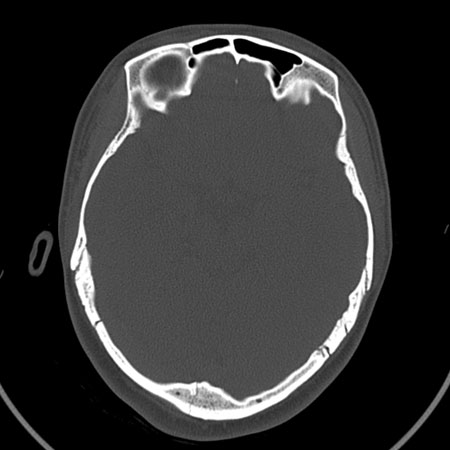

请问各位战友:图示箭头处是否为颅骨骨折?

病史:患者,女,20岁.头部及腹部外伤20分钟.伤后昏迷,无呕吐.头及右侧腰背部疼痛,双侧瞳孔等大,

右肾区叩痛.其它无异常.患者家属否认原有外伤史.

请大家看看是否为颅骨骨折.还是正常变异,或为陈旧骨折.谢谢.

图片未上传完,所见图象示枕骨线样低密度影,边缘锐利,结合外伤史,伤后昏迷,骨折不能除外。

枕骨的线样低密度影锐利、清晰,但正好位于矢状缝的位置,局部无明显软组织肿块,相临及对冲部位脑实质亦无出血及挫裂伤表现。

单就这几层暂不考虑骨折,建议上传完整图片。

楼主所关心的另一个线样影应该是头颅矢状面略偏左,射线正好穿过所致,不需要考虑骨折。

枕骨是单块的,矢状缝是在顶骨而不是在枕骨,枕骨后缘见线状低密度,边缘税利,考虑在骨折存在。

枕后部及左侧颞枕部边缘锐利的线样低密度影,局部软组织无异常,左侧乳突蜂房密度均匀,硬膜下及脑实质内未见出血灶,考虑为正常变异。

枕部考虑骨折。一般的颅逢不会跨越板障,楼主所示枕骨断面两侧板障也不连续。